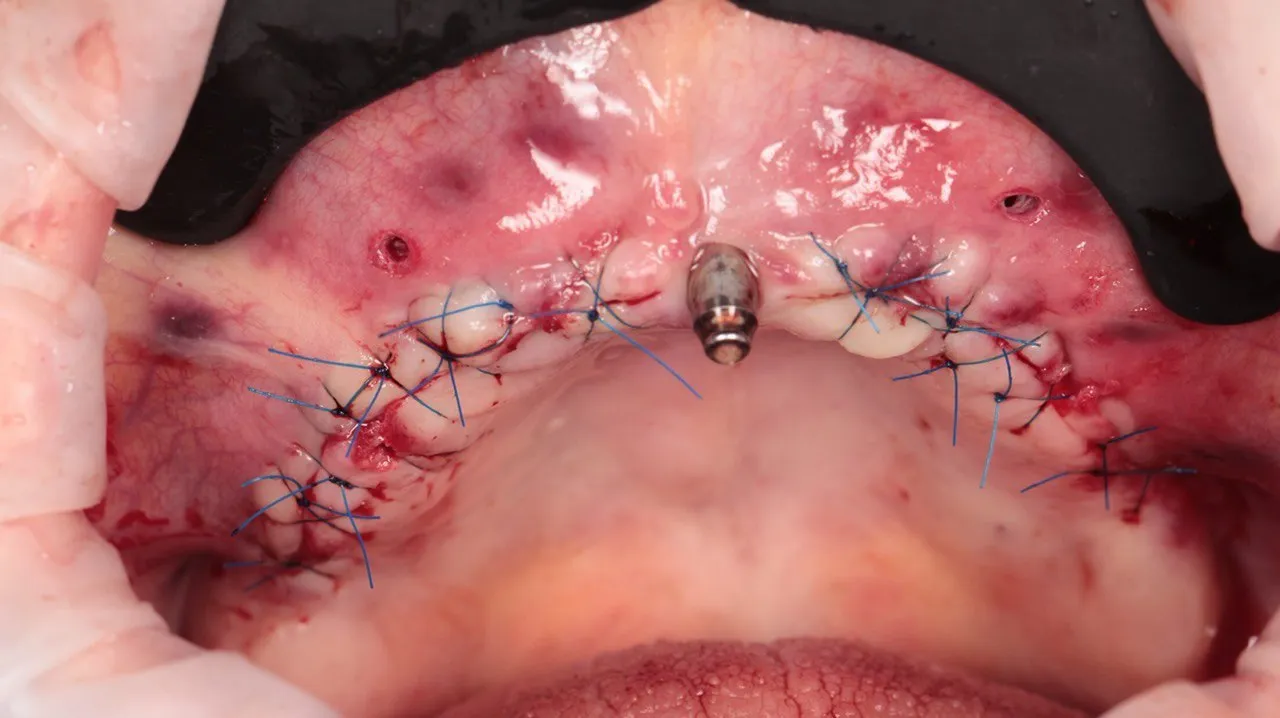

Clinical Surgical Guide Cases

Before-and-after dental implant surgery with guided protocols

Guided implant placement with simultaneous bone augmentation